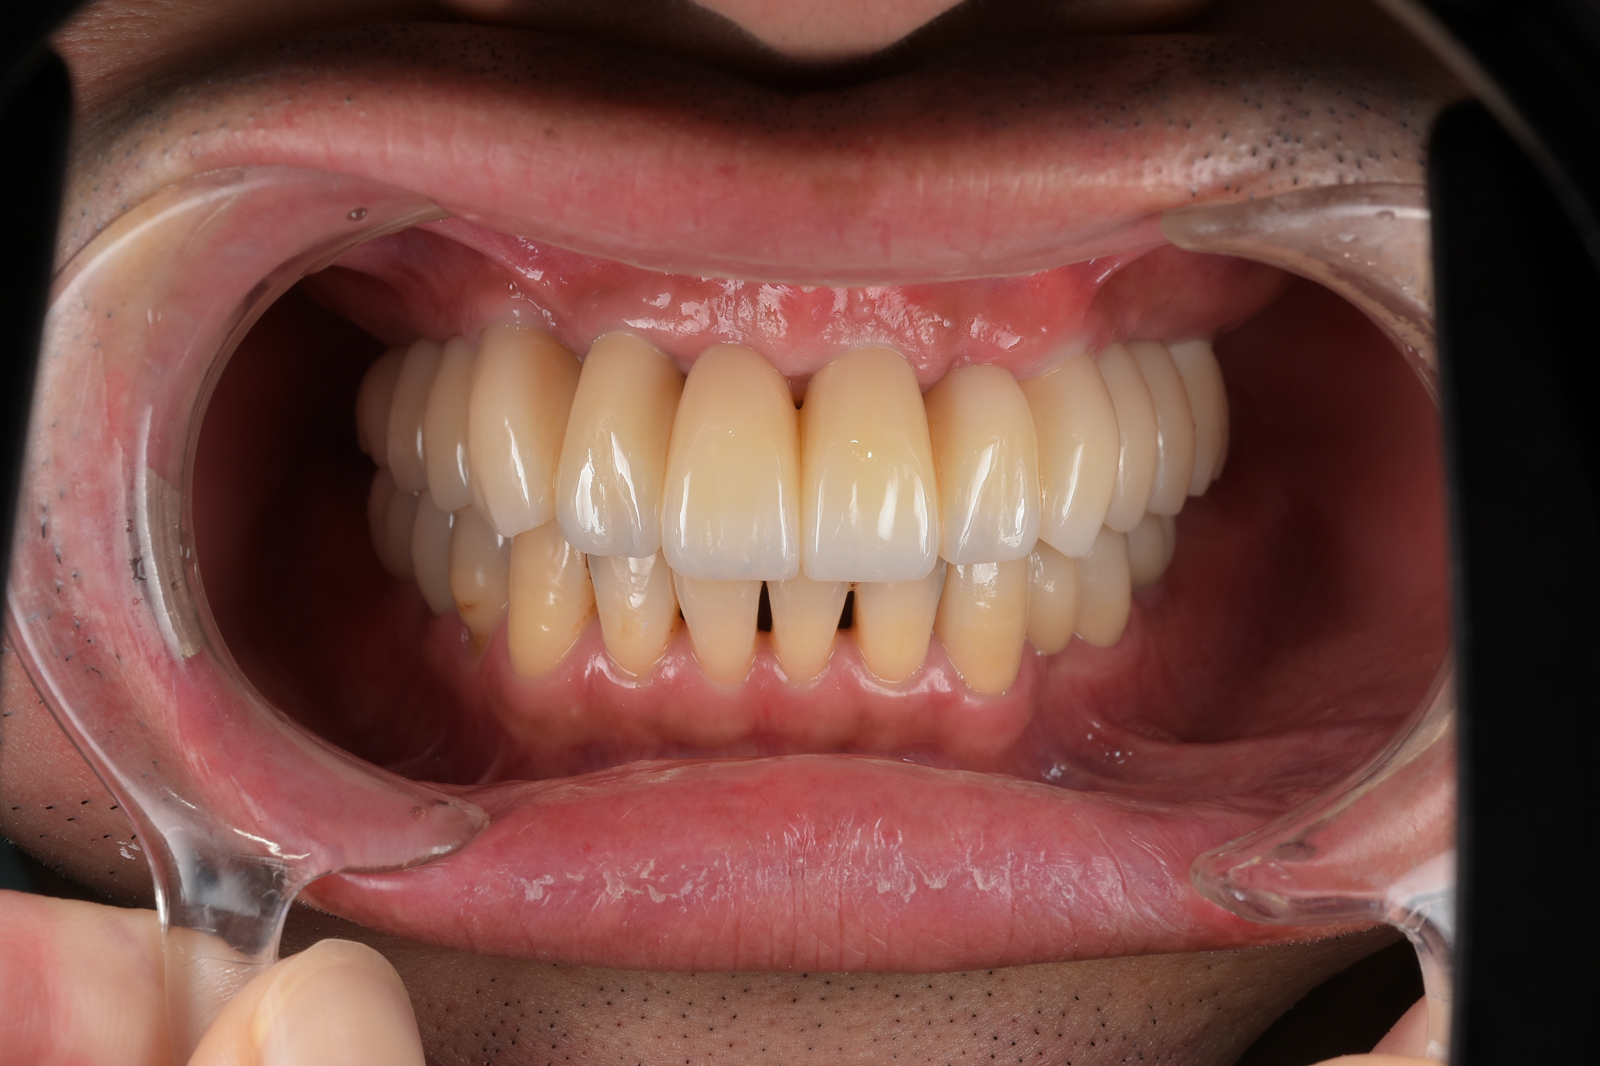

病状が進んで歯周ポケットが深くなってくると、治療器具が届かなくなり、通常の方法では歯石を取り除けなくなります。このような場合、外科的に歯肉を切開して歯石を取り除く「歯周外科治療」を行います。

歯肉を切り開いて、奥深くの歯石を取り除く治療法です。直接目で見ながら歯石を取り除くので、取り残しがほとんどありません。

こういった症例に効果的な治療法が、ルートセパレーションです。歯を2〜3に分割して掃除しやすくした上で、かぶせ物を装着して見た目や機能を回復させます。